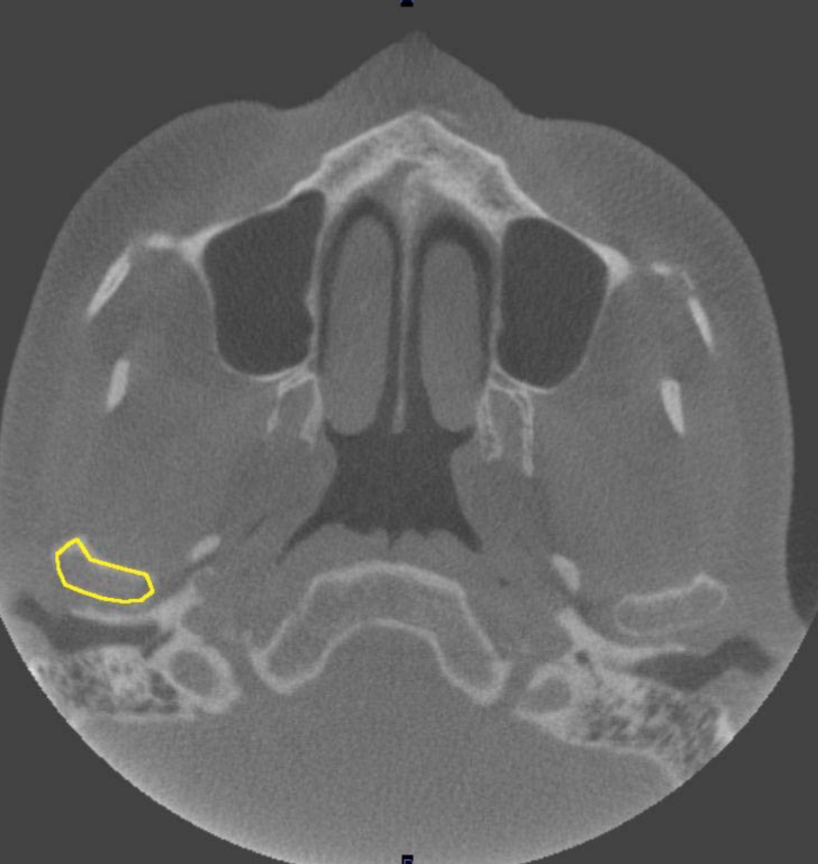

zygomatic arch

what is indicated by the YELLOW